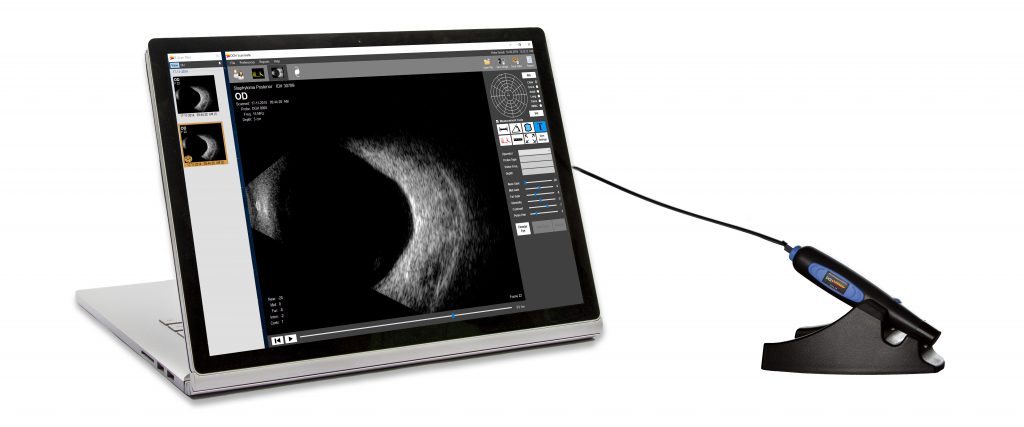

The DGH 8000 B-Scan combines the most advanced ultrasound technology available with the processing power, data storage and connectivity advantages of a personal computer. The DGH 8000 is equipped with dual 12.5 MHz and 15 MHz frequencies in the same probe, which results in a unique depth selection range from 3 cm and 6 cm in 12.5 MHz mode and 5 cm and 10 cm in 15 MHz mode.

It is a self-contained portable imaging system that interfaces with a Windows® computer via a USB 2.0 port. High resolution video loops and still images are obtained rapidly, and post processing features include playback, gain adjustment, contrast and image intensity variation, distortion-free zoom, distance, angle and area measurement and annotation tools. Patient data can be stored on a local computer or on a centralized network location where it can be accessed by multiple users. Patient records are fully searchable and can be exported in a format that is compatible with EMR/EHR systems.

TOTAL SOFTWARE SOLUTION

The Scanmate Software combines the most advanced ultrasound technology available with the processing power, data storage and connectivity advantages of a personal computer. Patient data can be stored on a local computer, or in a centralized network where it can be accessed by multiple users. Patient records are fully searchable and can be exported in a format that is compatible with EMR/EHR systems. The Scanmate software is designed to work on a Windows® computer. The DGH 8000 Scanmate B plugs into the USB 2.0 port of a Windows® computer that you may already have in your office or clinic*.

The software was designed to accomplish an examination in 4 simple steps.

Step 1: Patient Data : Populate the necessary fields and you are ready to acquire images.

Step 2: Acquire Images: Click on desired modality icon, and start acquiring images and data.

Step 3: Image Quantification and Processing: The software offers tools to measure distance, area, and angles, and an annotation tool for notating images. Images can be enhanced by adjusting intensity, contrast, and gains (near, mid, and far).

Step 4: Reporting: The Scanmate Software offers a variety of report templates that summarize critical information and are print and .PDF ready.